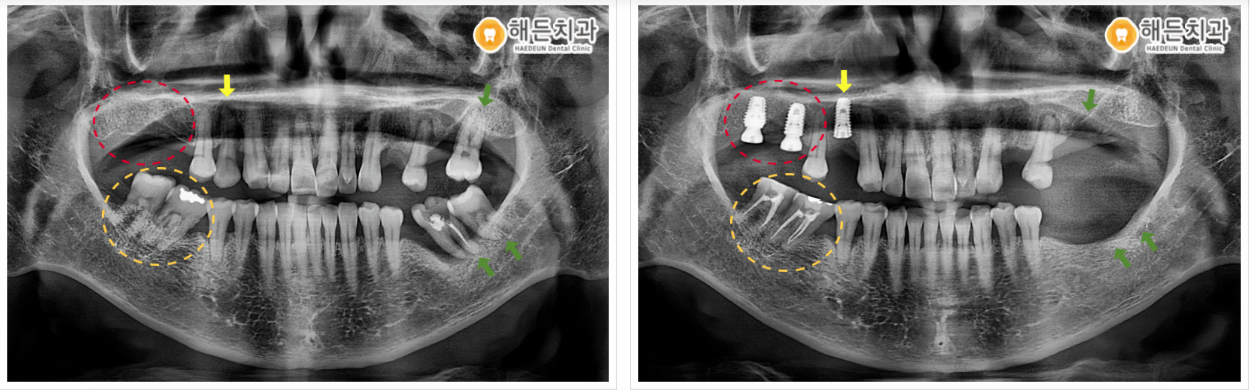

오른쪽 위턱 첫 번째 작은 어금니(#14)는 발치 후 주변 염증을 깨끗하게 제거한 뒤 잇몸뼈가 어느 정도 차오를 때까지 기다린 후에 임플란트 식립을 도와드렸으며, 큰 어금니 (#16,17) 부위는 잇몸뼈의 양과 주변 컨디션이 좋아 바로 식립을 도와드렸습니다.

위턱 어금니(#16,17) 임플란트 보철물이 올라가는 작업이 진행되기 전까지 맞물리는 아래턱 어금니(#47,48) 부위의 신경치료를 깨끗하고 깔끔하게 도와드린 뒤 차후 위아래 교합을 맞춰 같이 보철물이 올라갈 예정입니다.

왼쪽 위아래 어금니 부위도 발치 후 잇몸뼈가 어느 정도 차고 아문 모습을 확인할 수 있는데요. 오른쪽 치료 마무리 후 왼쪽 치료 계획 상담을 도와드릴 예정입니다. ^^

🦷 전 >후 🦷